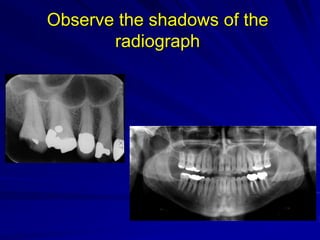

Observe the shadows of the radiograph

Observe the shadows of the

radiograph